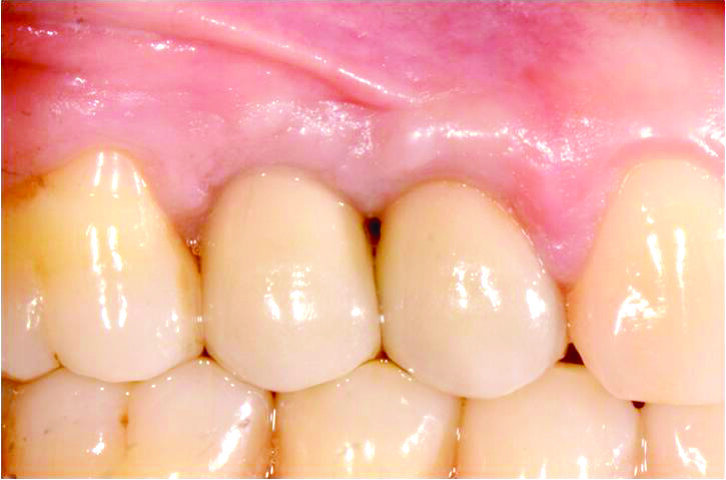

Il profilo di emergenza ottenuto con i provvisori è stato trasferito al restauro definitivo. Il caso è stato completato dopo 4 mesi dalla chirurgia con 2 corone in zirconia monolitica avvitate (Laboratorio Mutone, Napoli). Il risultato finale mostra la completa copertura dell’abutment e la presenza di tessuti tonici e privi di infiammazione (Figg. 12-14).

Fig. 12-14_Corone definitive e rx di controllo a due anni dalla chirurgia.